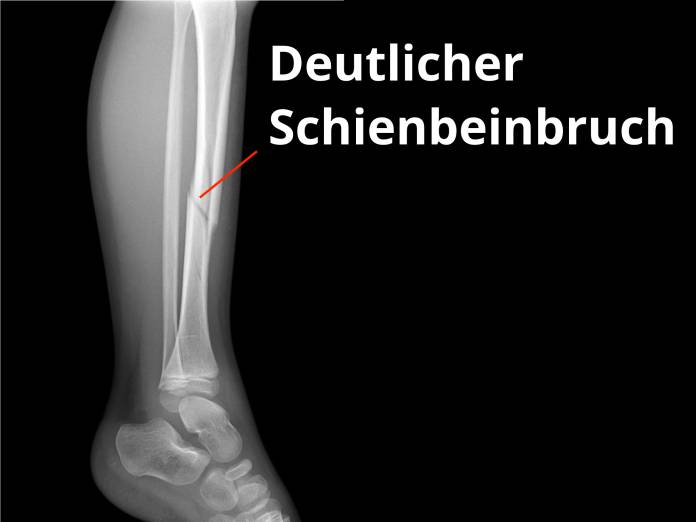

Der Schienbeinbruch (Tibiafraktur) ist einer der möglichen Knochenbrüche am Unterschenkel. Der Unterschenkel besteht aus zwei Knochen, dem Schienbein (Tibia) und dem annähernd parallel dazu laufenden Wadenbein (Fibula). Dabei ist das Schienbein in den meisten Bereichen dicker als das Wadenbein und trägt auch einen Großteil des Gewichtes. Ein Bruch des Schienbeins ist daher auch bedeutsamer als ein Bruch des Wadenbeins. Das Schienbein fällt als der Knochen am Unterschenkel auf, dessen Vorderrand unter der Haut tastbar ist. Es bildet mit seinem verdickten Anfang, dem Schienbeinkopf, einen Teil des Kniegelenks und mit dem Innenknöchel einen Teil des Sprunggelenks.

Als bildgebende Untersuchung genügt meist ein Röntgen, auch um den genauen Bruchverlauf zu sehen. Verletzungen der Umgebung des Knochens müssen aber ebenfalls beurteilt werden. So muss gegebenenfalls bei möglichen Gefäßschäden ein spezielles Ultraschall (Doppler-Sonografie) oder eine Röntgenuntersuchung mit Kontrastmittel (Angiographie) durchgeführt werden. Auch kommt bisweilen eine Computertomografie (CT) oder ein MRT (Magnetresonanz- oder Kernspintomographie) zum Einsatz.